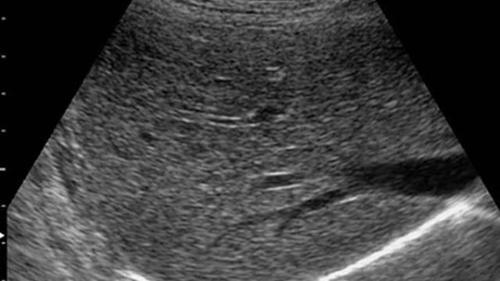

B超检查

现在的B超或者是彩超检查,通常是为了发现肝脏上面是否有结节,有没有出现肝硬化;或者出现了早期的小于2公分的肝癌细胞;以及是否有光点增粗密集,比如脂肪肝的症状。